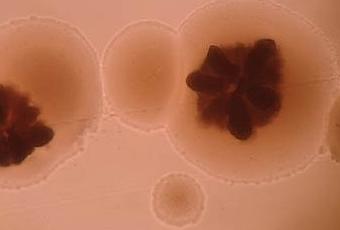

<span title="When researchers conducted analysis to see what could be causing these high citrullinated proteins, they found several potential groups of bacteria, but one single bacterial species called Aggregatibacter actinomycetemcomitans (Aα) emerged as the most likely candidate.

« >Aαdéclencheur de l’auto-immunité dans la polyarthrite rhumatoïde : plusieurs groupes de bactéries peuvent causer ces niveaux de protéines citrullinées élevés, mais une seule espèce bactérienne, Aggregatibacter actinomycetemcomitans (Aα) se révèle ici comme le candidat le plus probable : Aa provoque une production élevée de protéines citrullinées dans un type particulier de globules blancs (neutrophiles), en produisant une toxine appelée leucotoxine A (LtxA). <span title="This toxin splits open neutrophil cells which releases citrullinated proteins.

« >Cette toxine divise les cellules neutrophiles ouvertes qui libèrent des protéines citrullinées. Ces protéines citrullinées identifiées dans le liquide créviculaire gingival présentent un chevauchement marqué avec celles trouvées dans le liquide articulaire des personnes atteintes de polyarthrite rhumatoïde, avec 44 protéines en commun (sur 86). Bref, Aαapparaît ici comme un agent bactérien déclencheur de l’auto-immunité dans la polyarthrite rhumatoïde.